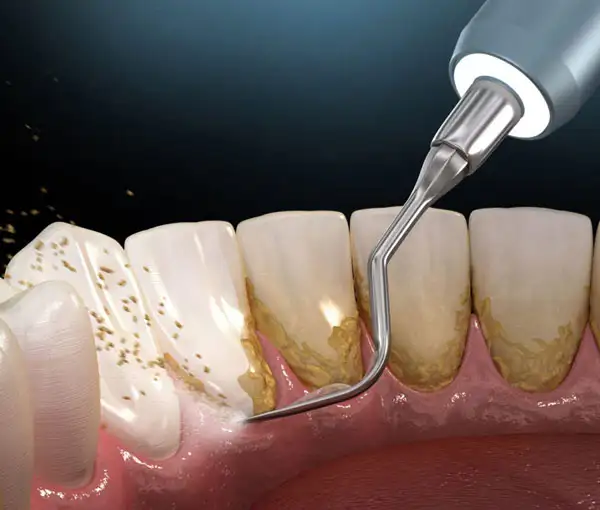

2. Teeth Cleaning (Scaling & Polishing)

Professional removal of plaque, tartar, and stains to prevent gum disease, bleeding gums, bad breath, and tooth decay. Polishing smoothens the teeth, making it harder for bacteria to stick. Regular cleaning keeps your smile bright and your gums healthy. Recommended once every 6 months for optimal oral hygiene.